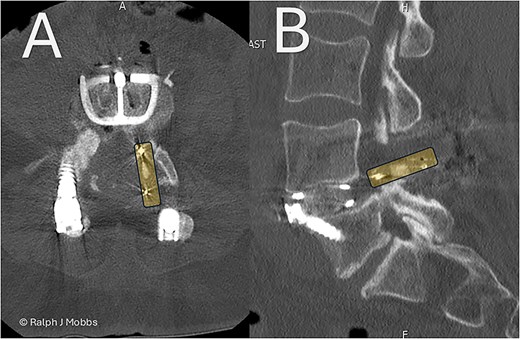

(A) Initial presentation with TLIF cage migration posteriorly into the spinal canal and paraspinal muscles. (B) Stage 1 and 2 completion, including revision fusion using an ALIF cage (Redmond Ti/PEEK, A-spine, Taiwan) and TLIF cage removal. (C) CT scan post TLIF removal and disc height restoration with ALIF cage.

A 64-year-old female with a history of a TLIF at L4/5, performed 18 months prior to presentation to the current surgeon, presented with persistent low back pain and radiculopathy. Imaging demonstrated non-union at the TLIF site with ongoing foraminal stenosis and segmental instability (Fig. 1A). Multidisciplinary review determined that a revision fusion was the initial focus as mechanical back pain related to non-union was the primary complaint. Following the planned stage 1 intervention, removal of the migrated TLIF cage was determined necessary as the device was serving no purpose and likely causing further symptoms. Therefore, a two-stage revision strategy was planned.

Day 1 postop ALIF. The PEEK cage can be seen in the canal and paraspinal regions. (A) Axial sequence. (B) Parasagittal sequence.